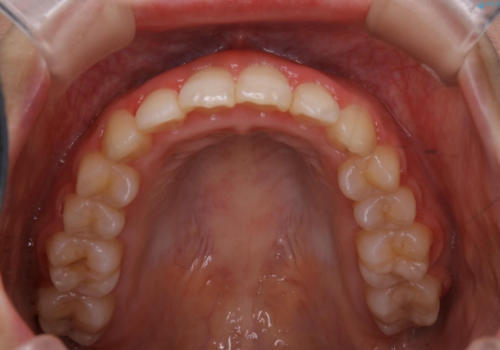

- 治療期間

- 7ヶ月

インビザラインは20時間以上の装着を厳守して頂くことで治療効果が期待できる治療となります。固定式のワイヤー装置に切り替えることで短期間で歯並びを整えることができ、大変喜んでいただけました。